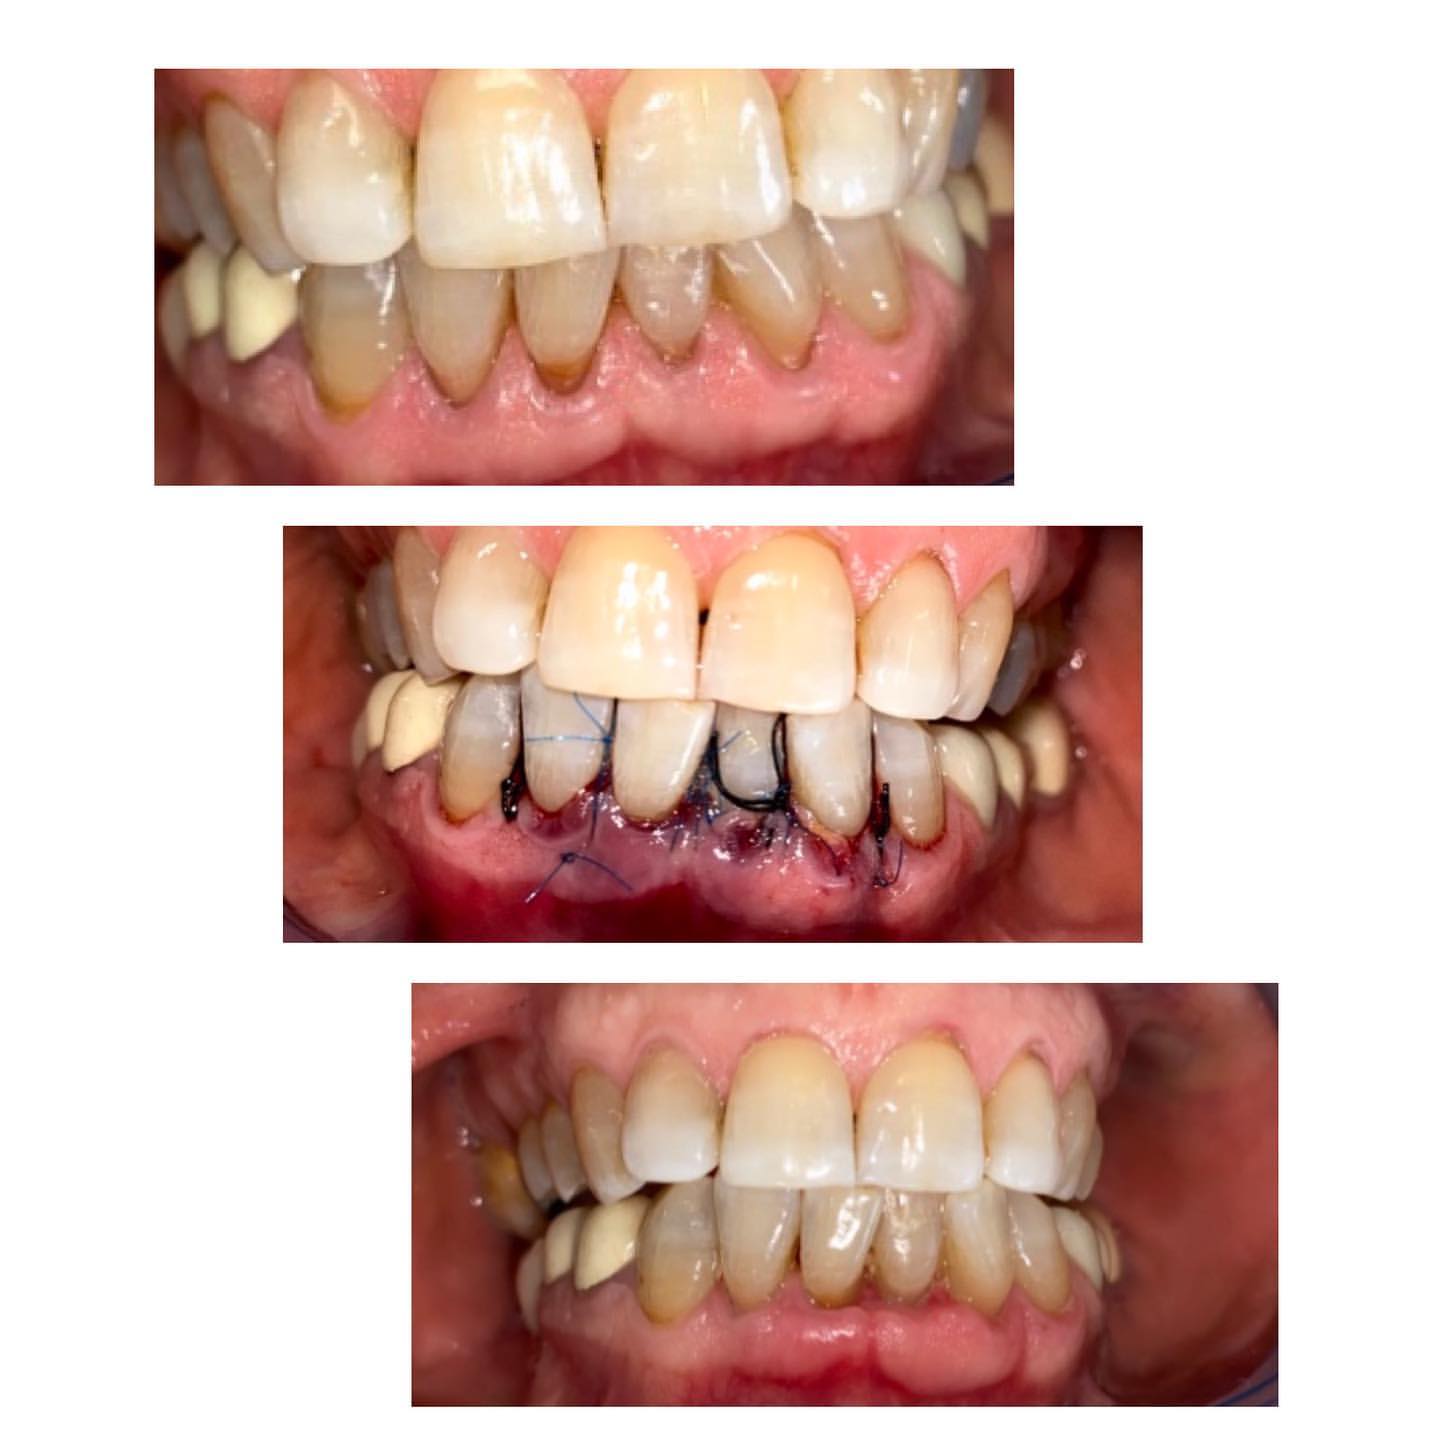

Diş ətinin iltihabı

Diş ətində olan qızartı, şişkinlik və qanama kimi əlamətləri olan diş əti xəstəlikləri müalicə olunmalı və sonra qapaq ilə implant edilməlidi